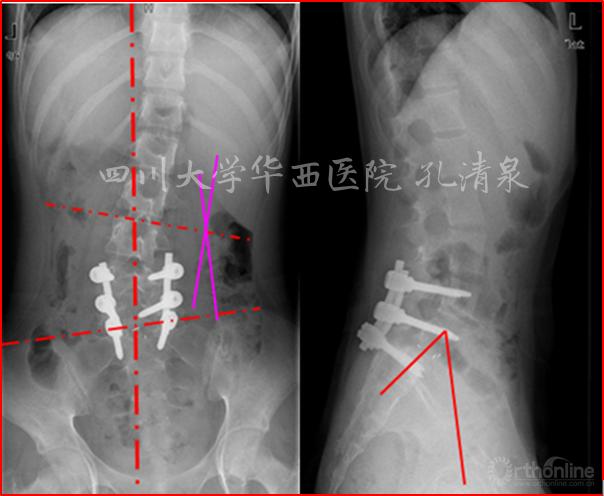

图9 术后一周复查见滑脱复位良好,无侧凸;术后两月复查,复位情况良好,可见轻微腰椎侧凸

图10 术后两年半复查提示腰段侧凸加重,整个冠状面平衡尚可